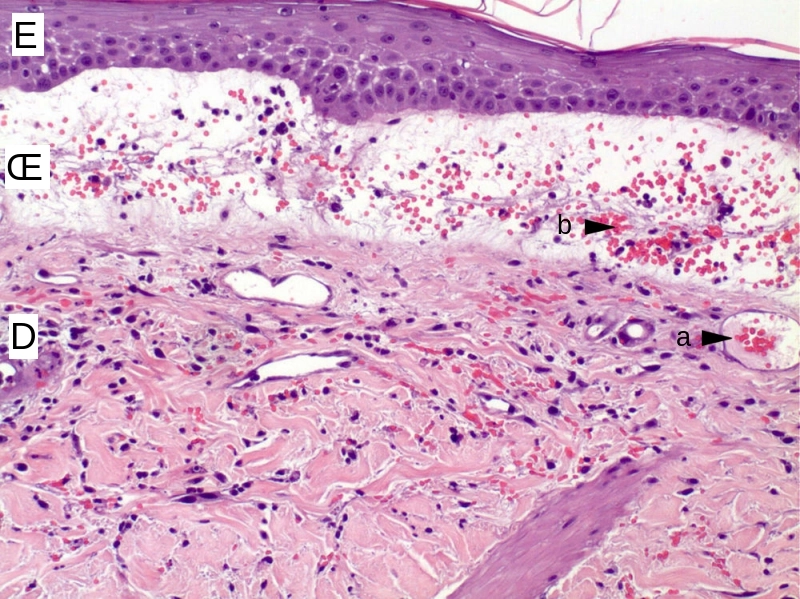

▲ Fig4: Examen histologique d'une biopsie réalisée sur le patient d'après (4).

(E = épiderme, Œ = œdème, D = derme, flèches a : hématies dans le vaisseau, b : hématies hors des vaisseaux)

La zone qui décolle l'épiderme du derme et dans laquelle on observe quelques hématies est formée par une exfiltration de plasma à partir des vaisseaux sanguins du derme. C'est un œdème.

Ces vésicules sont associées à des démangeaisons intenses. Elles correspondent à une réaction inflammatoire aiguë (RIA) localisée sur la peau et ayant une composante hémorragique (globules rouges hors des vaisseaux sanguins) (Fig4). Il s'agit donc d'une dermatite avec une composante purpurique (*).